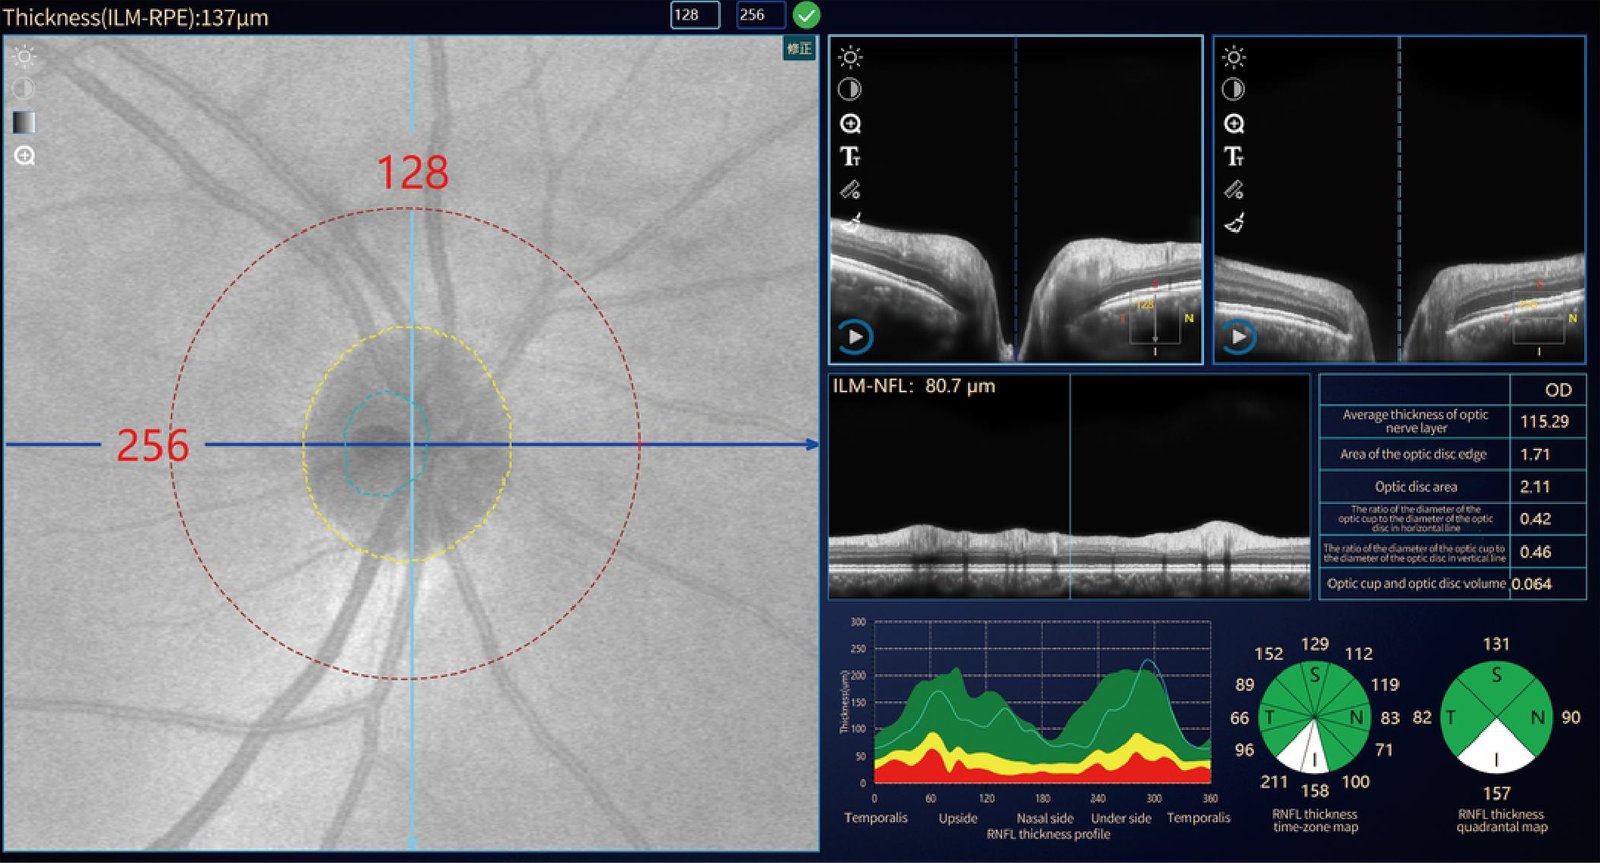

Glaucoma & macula detection - Automatic analysis

Glaucoma optic disc analysis | Optic disc data analysis • Thickness of RNFL • Thickness time zone • Quadrant chart